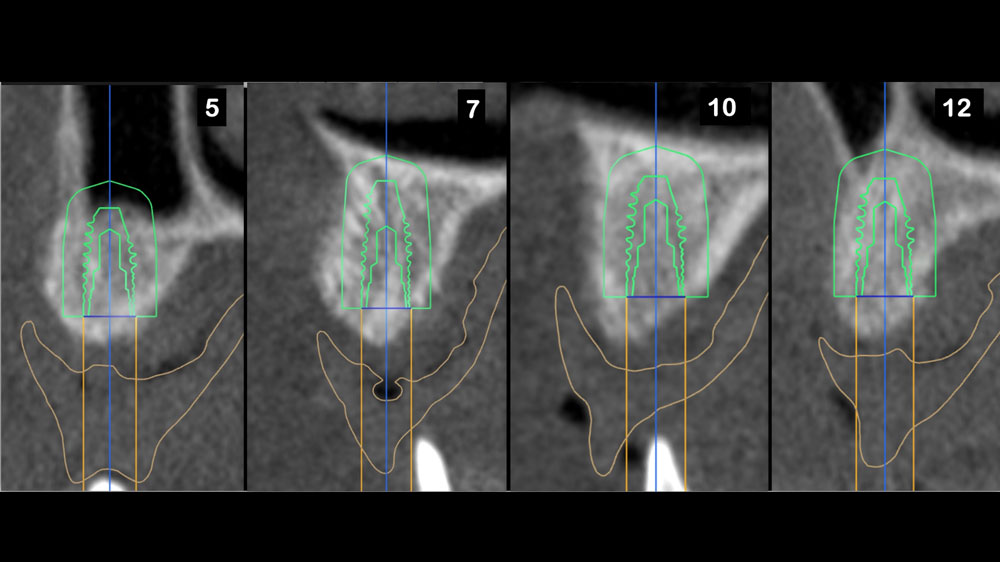

A 26-year-old edentulous female presented for implant-supported maxillary rehabilitation. She was systemically healthy and classified as ASA I. Clinical and radiographic evaluation revealed a Seibert Class III maxillary ridge defect with combined horizontal and vertical deficiencies. The patient exhibited a medium smile line and reported a highly active lifestyle with regular physical activity, indicating the need for a stable, durable, and esthetically driven implant rehabilitation capable of meeting long-term functional demands.

Horizontal (5–7 mm) and vertical (3–4 mm) ridge augmentation were successfully obtained, with stablewound management achieved through precise suturing techniques. The osteoinductive properties of the large vallos®, demineralized granules combined with rhPDGF-BB, a component of GEM21S® promoted high-quality bone regeneration, whereas the large Geistlich Bio‑Oss®, xenograft particles contributed to volume preservation by moderating resorption. As a result, four 4.3 mm implants were placed with high primary stability, each exceeding 35 N·cm of insertion torque, providing a strong foundation for a predictable esthetic and functional restoration.